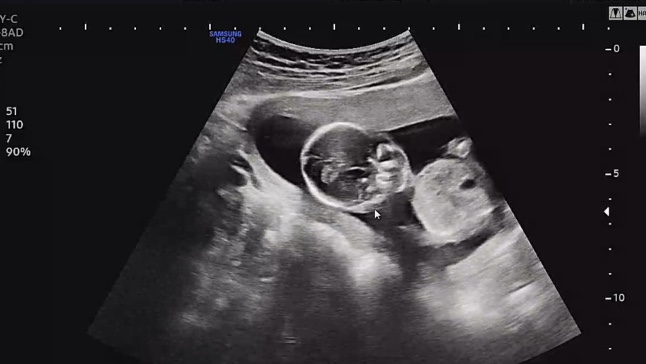

[임신 기록 : 둘째] 19주 23주 임신 기록. 파티마 여성 병원 임당 검사. 정밀 초음파.

오랜만에 쓰는 19주 차, 23주 차 둘째 임신 기록! 장꼬맹을 출산했던 병원은 이제 분만을 안 한다고,, 분만...

[임신 기록 : 둘째] 11주 15주 18주 임신 기록. 기형아 검사와 성별 확인

한방이의 임신 기록, 11주, 15주, 18주의 한방이. 안정기가 들어서니, 첫째랑 둘째랑 다름이 느껴진다(?) 2...